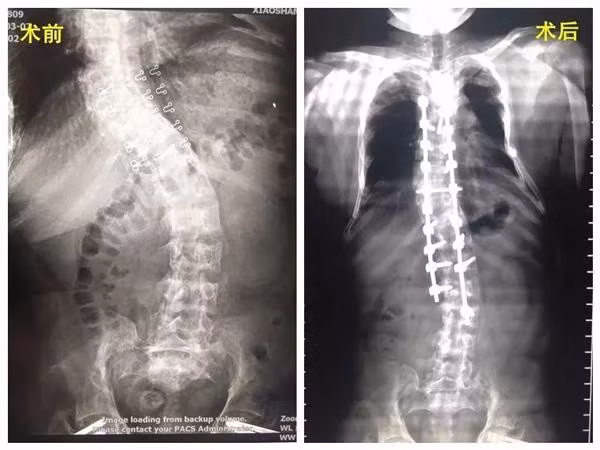

Thấy con gái có biểu hiện lạ, gia đình đã đưa Tiểu Hoa đến Bệnh viện Y học cổ truyền ở Tiêu Sơn để khám bệnh. Sau khi chụp chiếu, bác sĩ nhận thấy cột sống của Tiểu Hoa đã bị uốn cong hình chữ S, là biểu hiện của bệnh vẹo cột sống. Ngoài ra, cô bé còn bị loãng xương nghiêm trọng, kiểm tra mật độ xương nhận thấy nó tương tư như của người già 70 tuổi.

Để có thể lấy lại chiều cao ban đầu, Tiểu Hoa đã phải trải qua một loạt ca phẫu thuật. Tháng 3/2017, khoa Phẫu thuật và ung thư xương của Bệnh viên y học cổ truyền ở Tiêu Sơn đã tiến hành cắt bỏ khối u khoang mũi và xương sường.

6 tháng sau, phẫu thuật tuyến giáp cho Tiểu Hoa, phục hồi sự trao đổi canxi và phốt pho như bình thường, mức độ loãng xương nhờ thế cũng được cải thiện. Tháng 3/2018, cô bé được tiến hành phẫu thuật vẹo cột sống. Hiện tại Tiểu Hoa đã hồi phục khá tốt và dần lấy lại được chiều cao ban đầu.